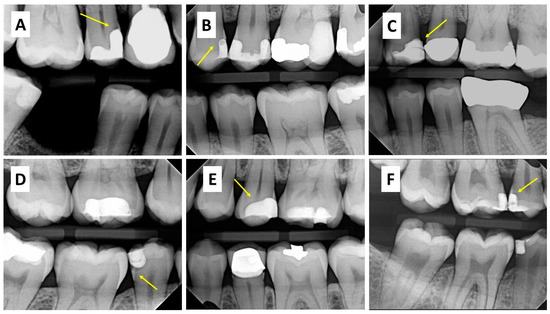

The 279 bitewings were categorized according to the type of material (composite or adhesive) and location (internal or external) (Table 1). The information recorded for each patient included age, sex, tooth, and restored surface. Guidelines were placed to avoid misinterpretation of bond interface radiolucency and secondary caries. Radiolucent areas detected at the cavity preparation walls were considered interfacial gaps. Large radiolucent regions not bound to the preparation structure and extending into the dentine were interpreted as secondary caries. The radiographic prevalence of atypical findings was presented as frequencies and percentages, whereas demographic variables were presented as frequencies and percentages when appropriate. Figure 3 displays a panel of radiographic images illustrating some of the radiolucences associated with Class II composite restorations. A. Secondary caries, B. Voids in the body of the composite, C. Interlayer lines within the body of composite, D. External gap, E. Internal gap, and F. Combination of void in the composite and internal gap at the bonding interface.

A panel of radiographic images illustrating some of the radiolucences found associated with Class II composite restorations (yellow arrows are highlighting the area of interests). (A) Secondary caries, (B) Voids in the body of the composite, (C) Interlayer lines within the body of composite, (D) External gap, (E) Internal gap, and (F) Combination of void in the composite and internal gap at the bonding interface.